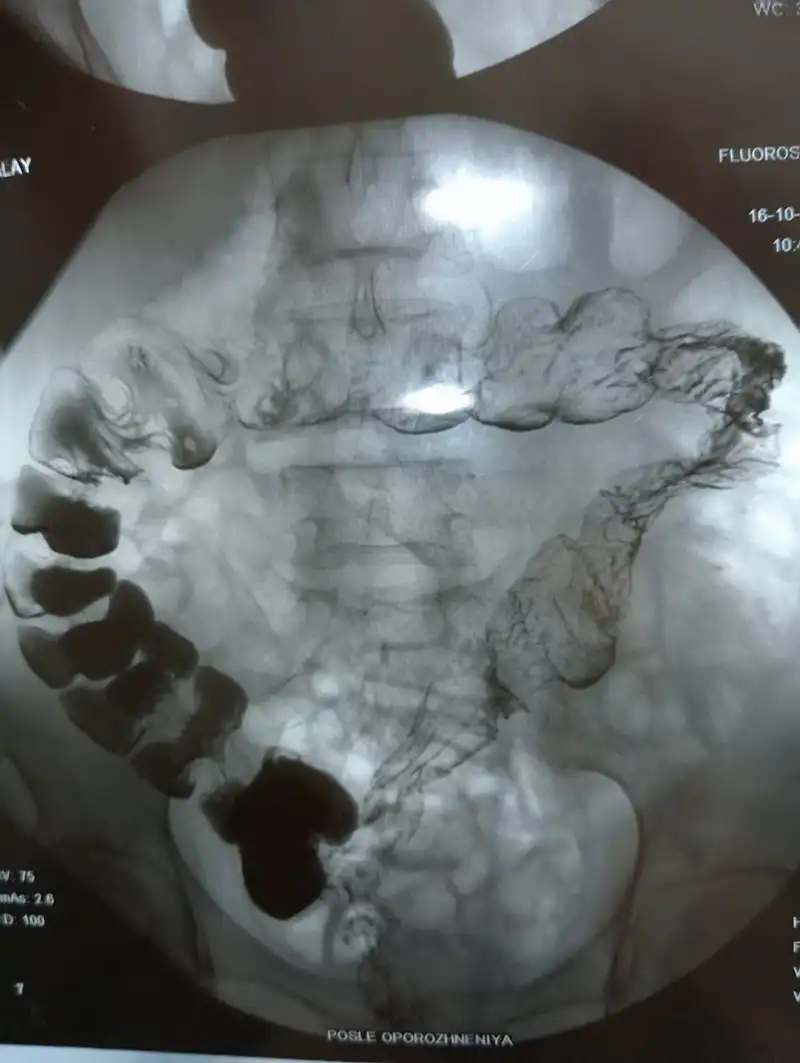

"Я жила с пожилыми родителями, и у нас не было денег на платные клиники. В больнице меня не направляли на обследования. Я начала бить тревогу, и меня направили на колоноскопию, но её провести не удалось из-за риска повреждения стенки кишки. В итоге мне сделали рентген, который показал, что кишечник был как баллон", — рассказывает Куралай.

Раздутый кишечник на рентген-снимке. Фото предоставлены Куралай Идрисовой